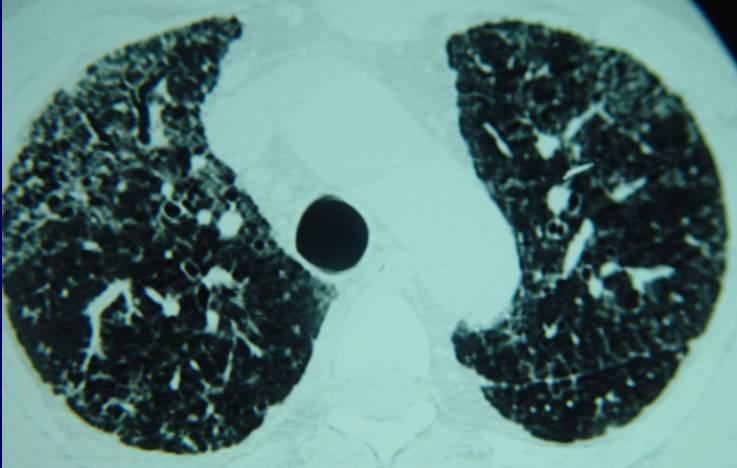

“你这个不是肺炎,也不是流行性感冒,应该是咳嗽性哮喘,而且有点年头了,左肺还出现了这么明显的阴影,初步判断是肺纤维化……”

呼吸科张主任看着年龄只有28岁的小伙子,感到非常的无奈,年纪如此轻却患上了咳嗽性哮喘,虽然这也不是什么绝症,可是因为他的乱用药,最终引起了肺部纤维化病变,而且这种病变是不可逆的,从今以后医生能做的只有延缓纤维化,无法治疗。

咳嗽性哮喘和感冒细菌引起的咳嗽症状十分相似,但是确实完全不同的两种疾病,而阿莫西林和头孢专治感冒细菌,因此对咳嗽性哮喘的治疗微乎其微,最终才导致小张肺部的细支气管末端损坏,出现纤维化。